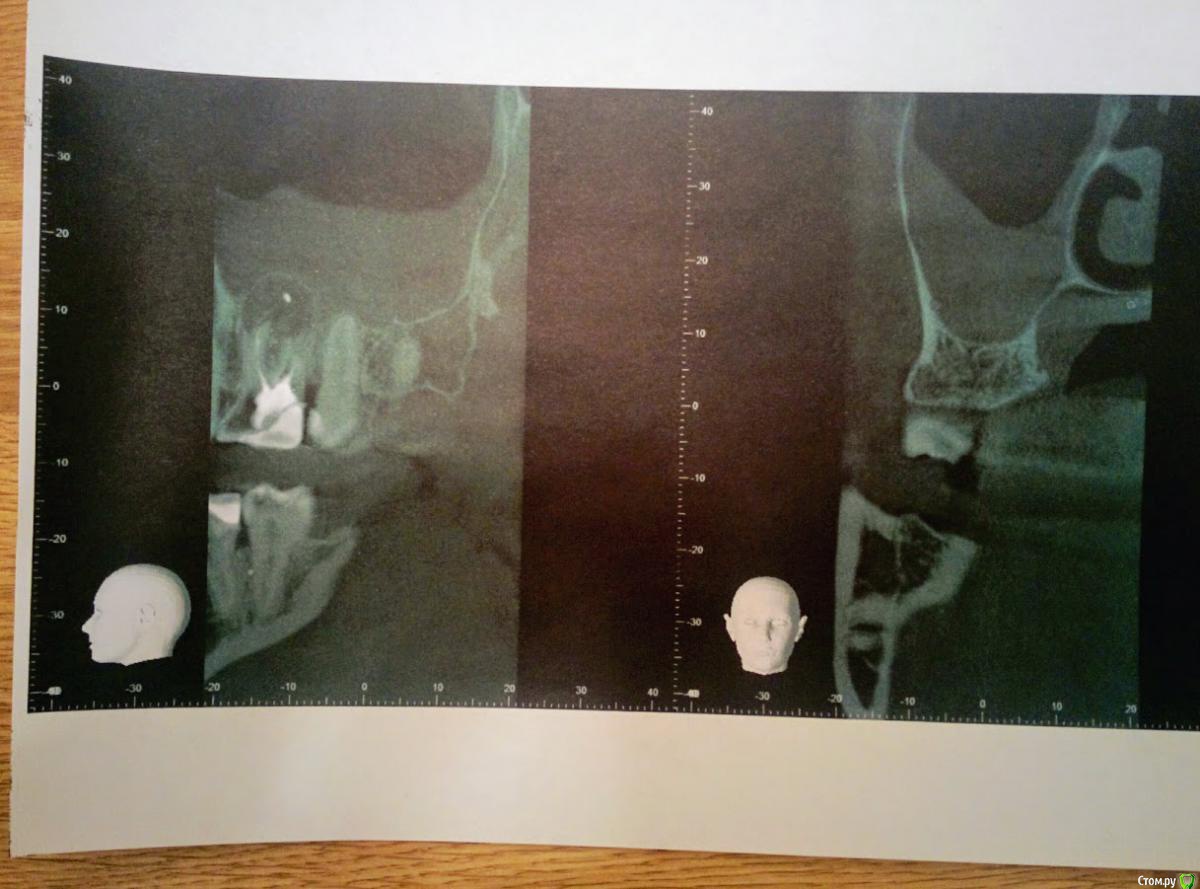

timson Опубликовано 18 марта, 2017 Поделиться Опубликовано 18 марта, 2017 (изменено) Здравствуйте, помогите советом пожалуйста. Ситуация сследующая: Почувствовал чувство давления справа вверху и внизу, врач терапевт осмотрел полость рта и пульпит не нашел.Направлен я был на ортопантомограмму https://yadi.sk/i/6HkZCRSm3FEaGc, на ней обнаружена ретенция 8 зуба мудрости справа.Обратился к стоматологу хирургу , у него сделана фрагментарная КТ правой стороны челюсти. https://yadi.sk/d/FdOB70aA3ErpHn -образ ктhttps://yadi.sk/d/cf0GB6vR3ErpHt программа в архиве deamons tools в rar архивеКто не знает, устанавливаем программу daemons tools, выбираем монтировать и указываем скаченный образ.В итоге обнаружена радиальная киста 6 зуба спрва вверху, из за предположительной причины, некачественная эндодонтия, не закрыты каналы.(Обратился в ЧЛХ отделение, где 6 зуб хотят удалить.После чего обратился в частную клинику, где врач стоматолог хирург позвонив в ЧЛХ отделение, посоветовавшись там с доктором, отказался заниматься этим зубом.За ретенированный зуб берется, просит 7000.Обратился по совету врача хирурга к опытному хирургу. Его заключение надо заняться 6 зубом и кистой-цена вопроса 5000, а для удаления ретинированного зуба рекомендовал депульпировать вначале 7 зуб, что бы избежать затем осложнений и сохранить 7 зуб. Хотелось бы сохранить зуб,не очень понятно почему нельзя удалить корни зубов и не удаляя зуб.Помогите кто может сталкивался с такой проблемой.Клиники гайморита пока слава Богу нет. Отмечается эпизодическое чувство давления снизу справа.Хотелось бы сохранить зуб, можно ли в данном случае сохранить зуб и какие варианты кто предложит.Так же интересует стоит ли идти на амбулаторное иссечение кисты или стационар ЧЛХ? Спасибо за внимание. Изменено 18 марта, 2017 пользователем timson Ссылка на комментарий